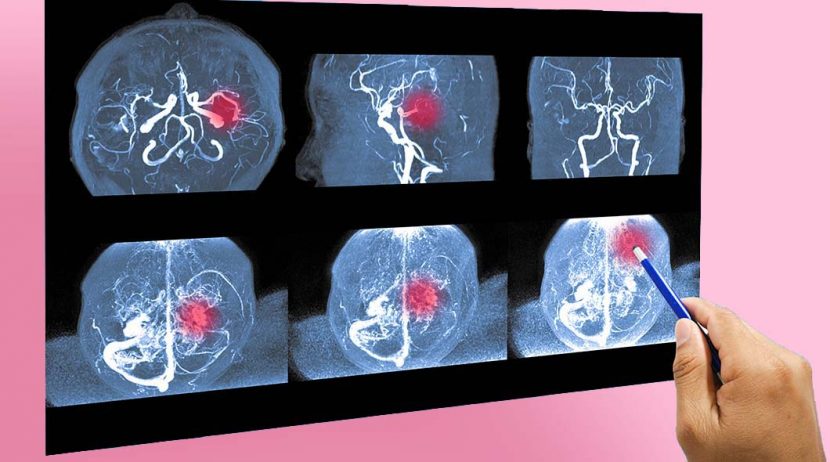

A angiografia é um tipo de raio-X em que se injeta um contraste nos vasos sanguíneos para se poder perceber  se estão saudáveis e se o sangue flui bem pelos mesmos. As imagens criadas pela angiografia chamam-se angiogramas.

A angiografia é um exame usado para ver a saúde dos vasos sanguíneos, ou seja, para ver se existem estreitamentos, bloqueios ou malformações nos vasos sanguíneos.

• Cerebral: vasos sanguíneos que suprem o cérebro.